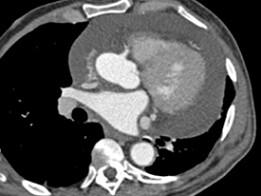

问题 男,28岁,胸闷气急,伴干咳,查体见颈静脉显露,CT如图,最可能的诊断为 ( )

选项 A、贫血性心脏病 B、心包转移瘤 C、心包积液 D、心肌炎 E、心包肥厚

答案 C